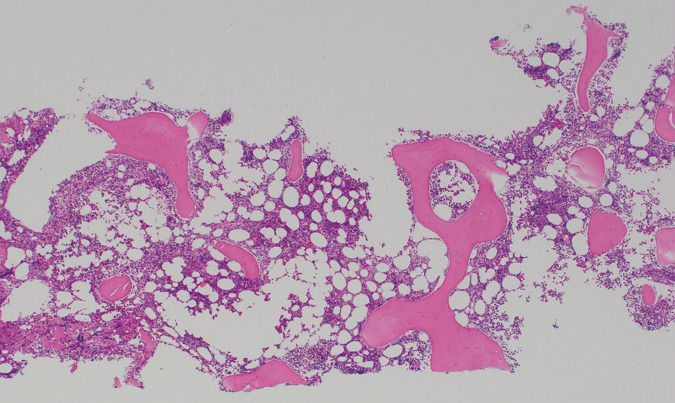

Case presentation: A 51-year-old woman was diagnosed with Stage II B TNBC and underwent NAC using pembrolizumab + paclitaxel + carboplatin. Her blood test on cycle 4, day 15 (C4D15) showed a significant decrease in platelets to <2000/μL accompanied by overt bleeding tendency. She was hospitalized for further investigation and treatment. Her platelet count recovered after platelet concentrate transfusion and corticosteroid administration. Her bone marrow examination showed normal cellularity, and she was judged as ITP. Due to the event and good clinical response to NAC, she underwent a right partial mastectomy and axillary lymph node dissection without completion of the planned NAC. The surgical specimen showed a complete pathological response.